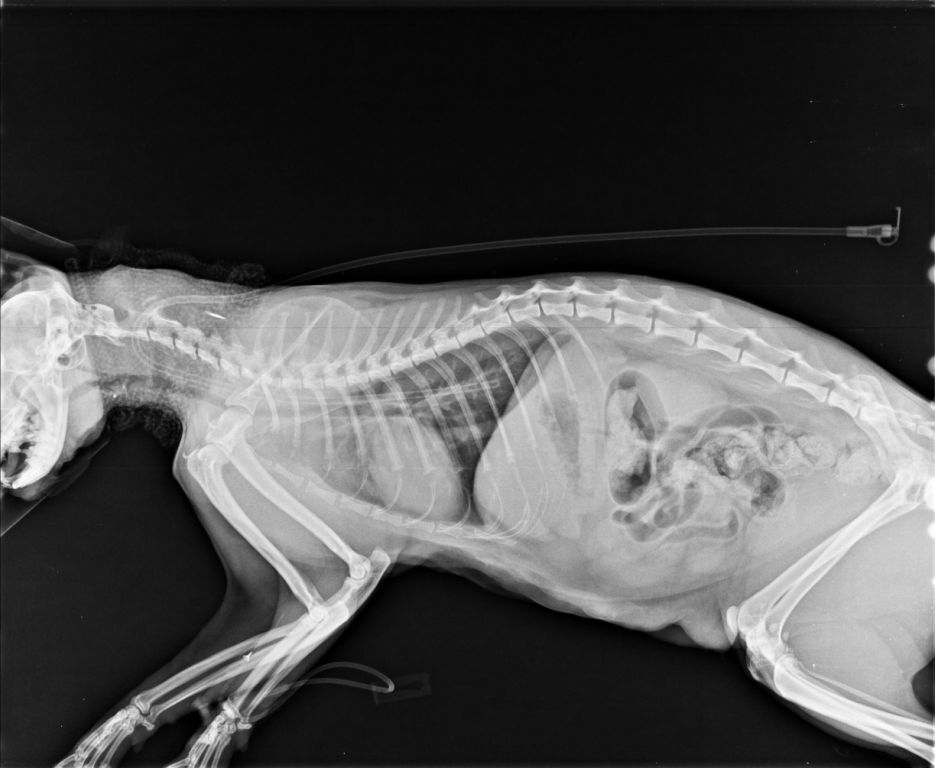

白親親於住院期間由於嚴重的口水不止以及鼻塞導致張口呼吸

不吃不喝因此院方替白親親裝設食道胃管

治療後逐漸穩定而出院

7/3 極光出院 白親親

【身體狀況】

頸部有食道胃管的縫合傷口,請注意白親親是否有搔抓。